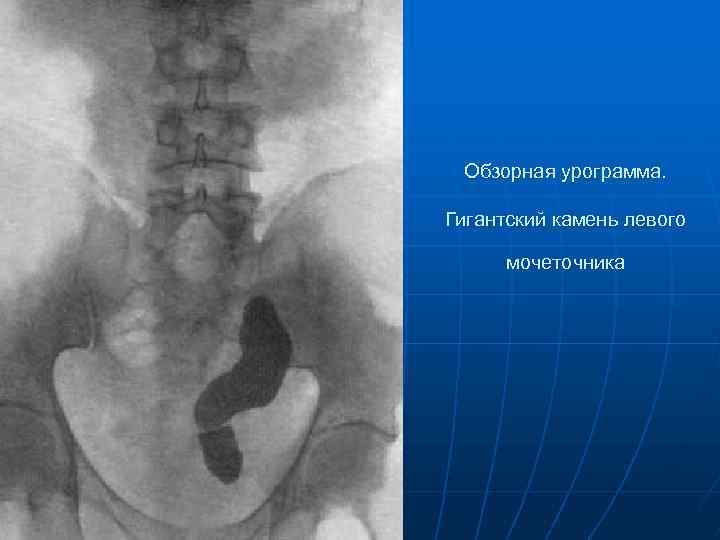

Рефлюксирующий мегауретер: Визуализация и медицинские изображения